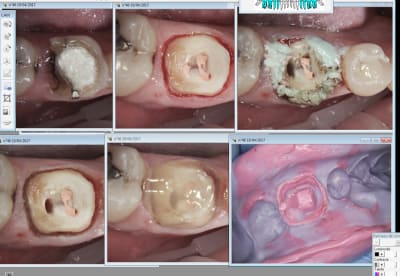

Non il n'y a pas de laser sur le cas précédent. Juste de l'expasyl. -)

Sur celui ci il y a laser.

Ici il y a un chouille de laser en distal.

Le cas avec les ic j'ai préparé le haut d'abord expasyl puis le bas expasyl puis empreinte du haut puis du bas.

Les autres je laisse l'expasyl le temps de faire le logement du tenon et de préparer le matos pour l'empreinte : 5 mn max.

Ah oui j'y colle un une lichette de rétragel avant d'appliquer l'expasyl. Radical. -)